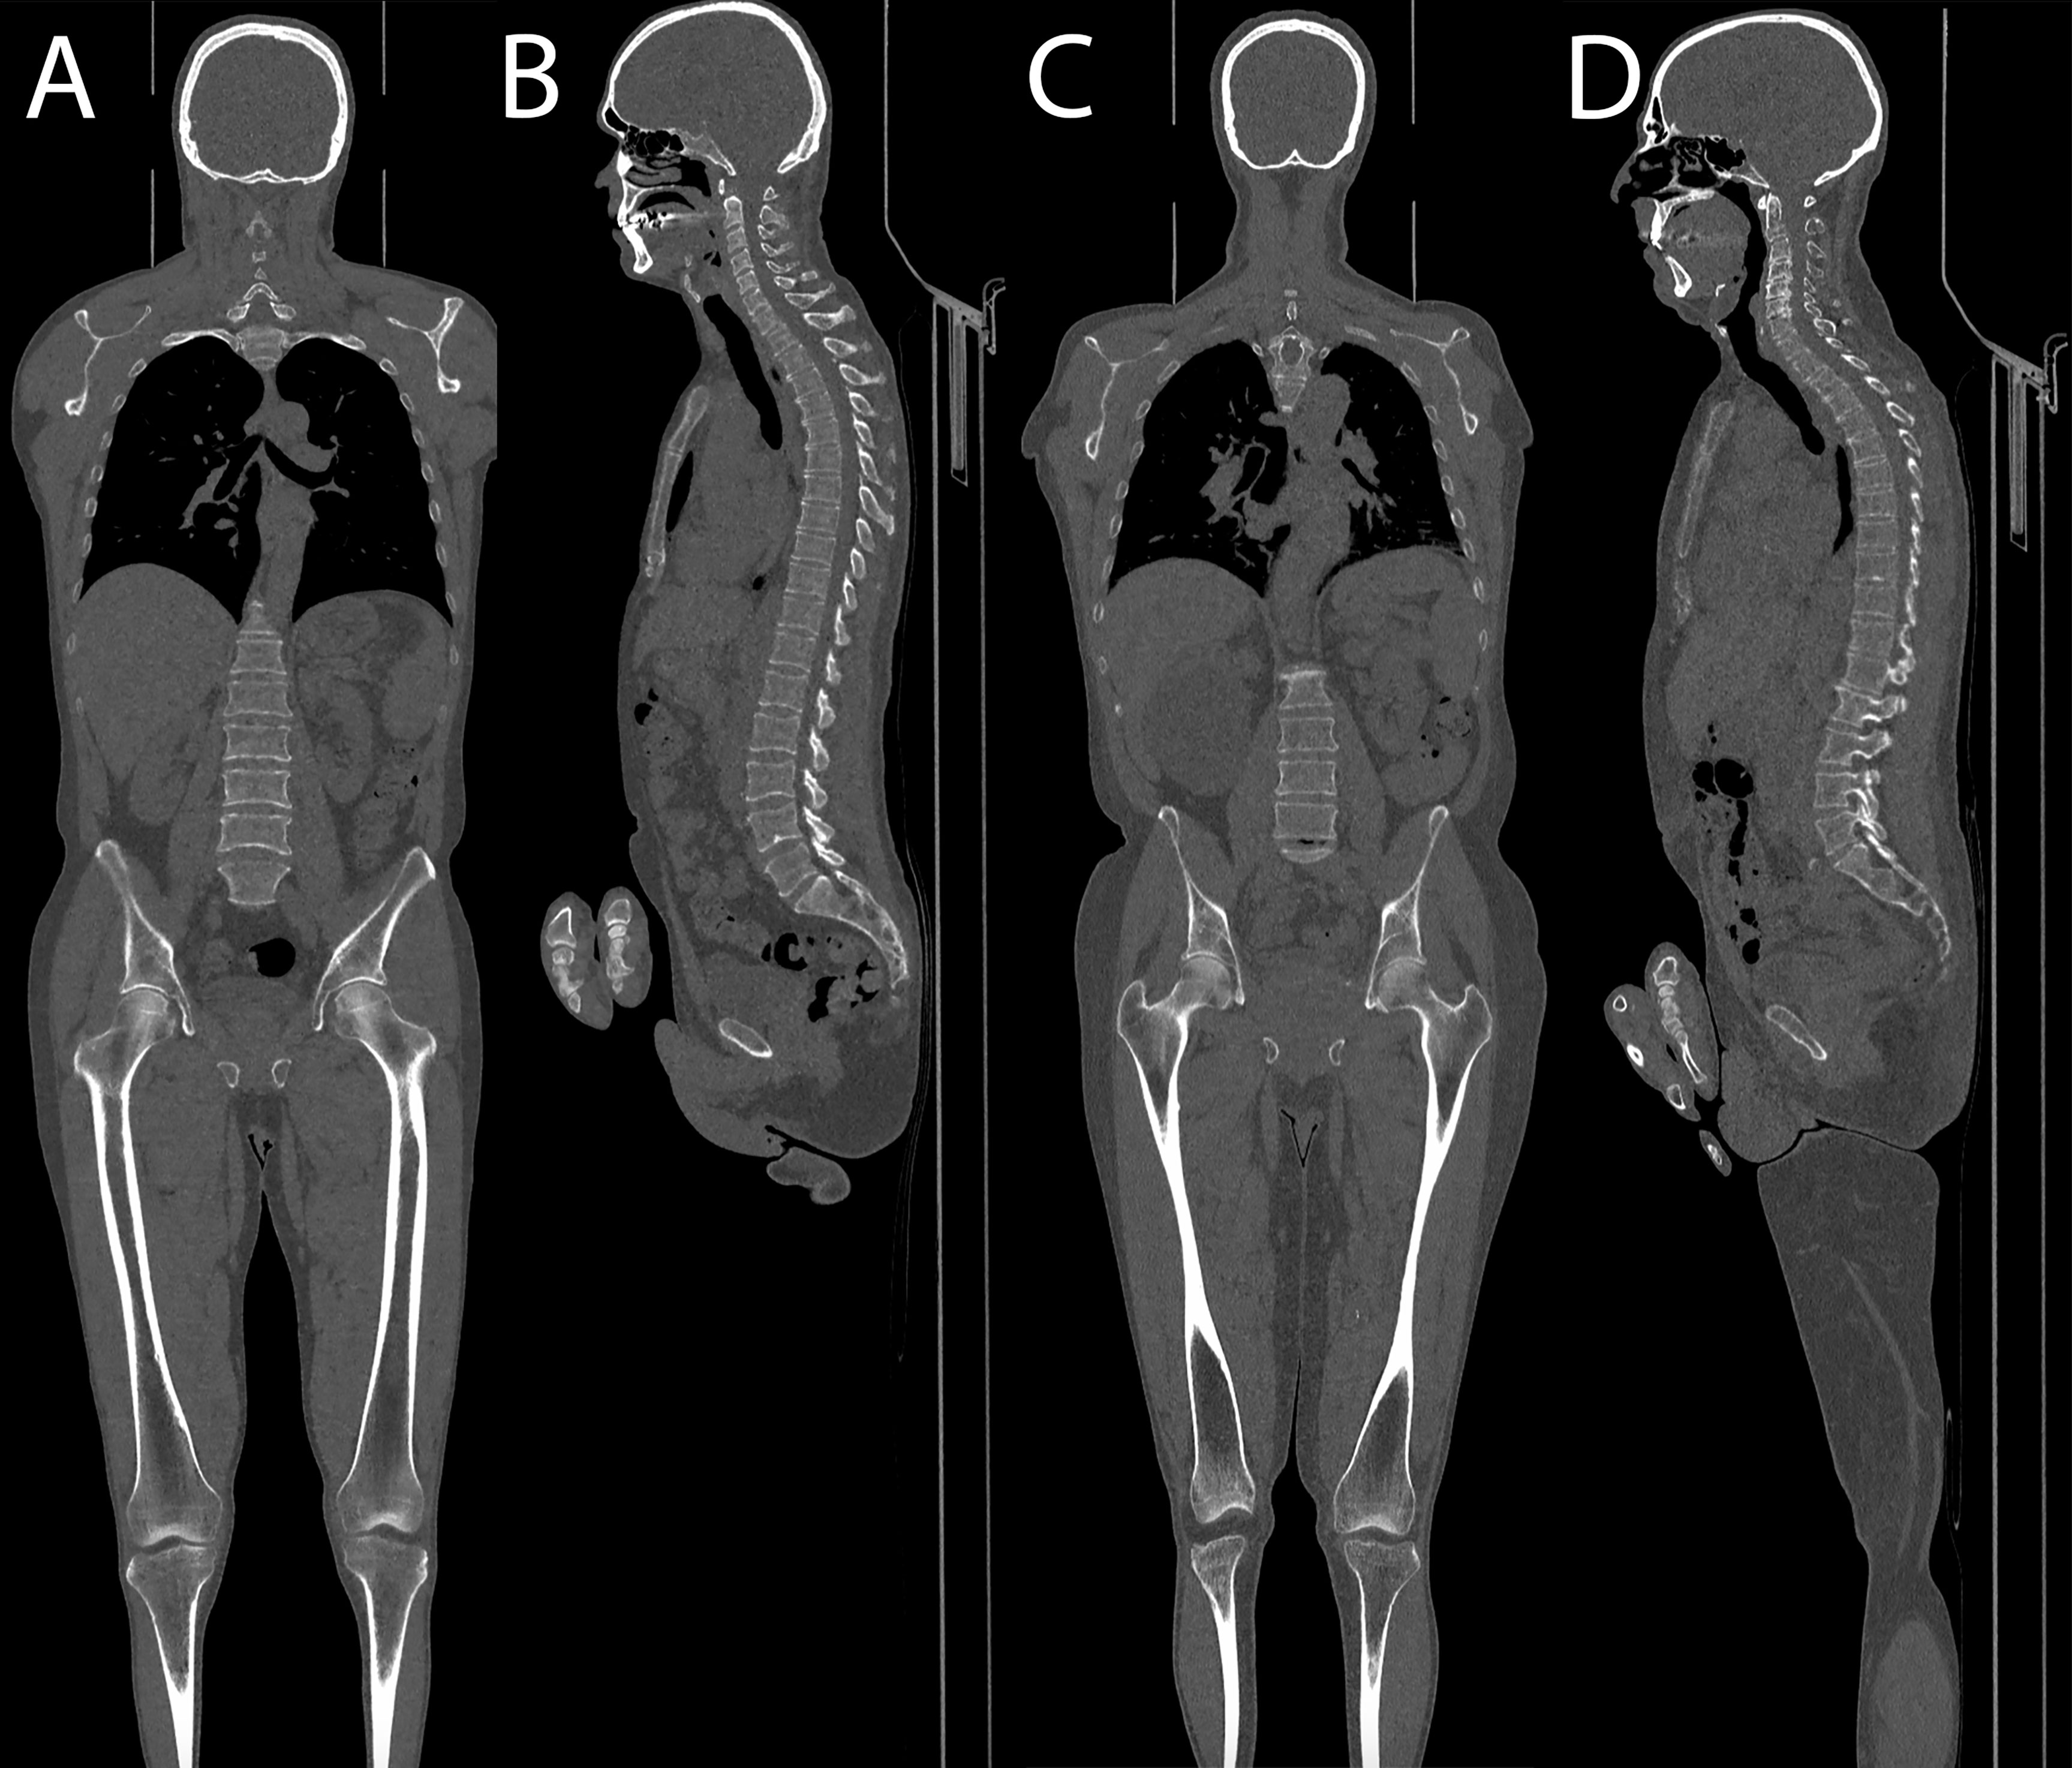

No statistically significant differences were demonstrated at Student’s t-test comparing mean Likert scores between standard and low-dose exams (respectively, mean score for skull, 4.94 vs. 4.93, p = 0.708; for thoracic spine, 4.88 vs. 4.89, p = 0.765; for pelvis, 4.94 vs. 4.94, p = 0.882; and for distal femora, 5 vs. 4.96, p = 0.097). Complete results are shown in Table 2. Sample images of a low-dose and standard protocol study are shown in Figure 5.

Figure 5 (A, B) Coronal and sagittal images of a patient acquired with the optimized protocol, total DLP of 157 mGy cm. (C, D) Coronal and sagittal images of a patient acquired with the standard protocol, total DLP of 434 mGy cm.